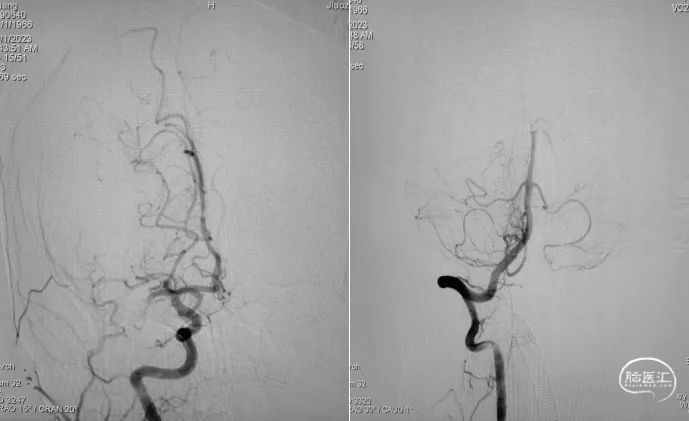

DSA提示:右侧大脑中动脉M1段以远闭塞,右侧大脑前动脉皮层支少量代偿,右侧大脑前动脉A3段血栓影,远端流速可,基底动脉尖端未见显影,考虑急性闭塞。

6F心玮吞川®颅内血栓抽吸导管同轴配合8F心玮天梯®支撑导管在泥鳅导丝导引下放置于右侧颈内动脉眼段。

微导丝配合微导管沿颅内血栓抽吸导管小心通过右侧大脑中动脉血栓段,微导管造影示右侧大脑中动脉远端血流通畅。

确定血栓长度后,以4.0*30mm颅内取栓支架行右侧大脑中动脉取栓配合中间导管抽吸。

造影提示右侧大脑中动脉血流通畅。

取栓装置中可见白色胶冻状血栓。

6F心玮吞川®颅内血栓抽吸导管行基底动脉血栓抽吸。

复查造影示基底动脉及其分支显影良好,取栓装置中可见白色胶冻状血栓。